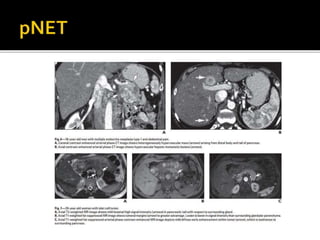

 pNET: conjunto de tu

gastroenteropancreaticos.

 Originados de células madre pluri-

potenciales del epitelio ductal.

 1-5% de todos los tu de páncreas.

 51-57 a , igual género, casos

esporádicos.

 NEM 1, SdVon Hippel- Lindau, NF I,

ET.

 Clasificación:

 Funcionantes. 15-52% se dividen de

acuerdo a la hormona que producen.

 No funcionantes.

 Tienden a ser múltiples ( NEM,VHL)

 Lesiones únicas: 90% de los

insulinomas.

 Lesiones múltiples 20-40%

gastrinomas.

 Tamaño variable.

 Funcionantes: + pequeños.

 No funcionantes: grandes x efecto de

masa. 90% malignos.

 Riesgo de malignidad aumenta con el

tamaño del tumor > 5 cm.

 Características morfológicas:

variables:

 Pequeños : homogéneos.

 Grandes: heterogéneos; deg quística/

necrótica.

 Malignos: invasión local, vascular, mtt.

 MRI:

 Tiempos de relajaciónT1 yT2 más

largos que el parénquima normal y

las otras neoplasias.

 Intensidad de señal

▪ baja enT1.

▪ Moderada –altaT2.

 Hipervasculares:

▪ Aumentan la intensidad ávidamente

durante la fase arterial.

▪ Realce homogéneo < 2 cm. Esencial

en insulinoma

▪ < 2 cm realce homogéneo.

▪ Fase portal: atenuación variable.

▪ Retraso atípico con realce portal.

 MTT:

▪ Hepáticas –linfáticas.

▪ Realce similar al tu primario.

▪ Caracterización TC doble fase, RM de

alta resolución.

 Dg insulinoma

▪ S: 85-64

▪ Tc: de doble fase delgado: 94%